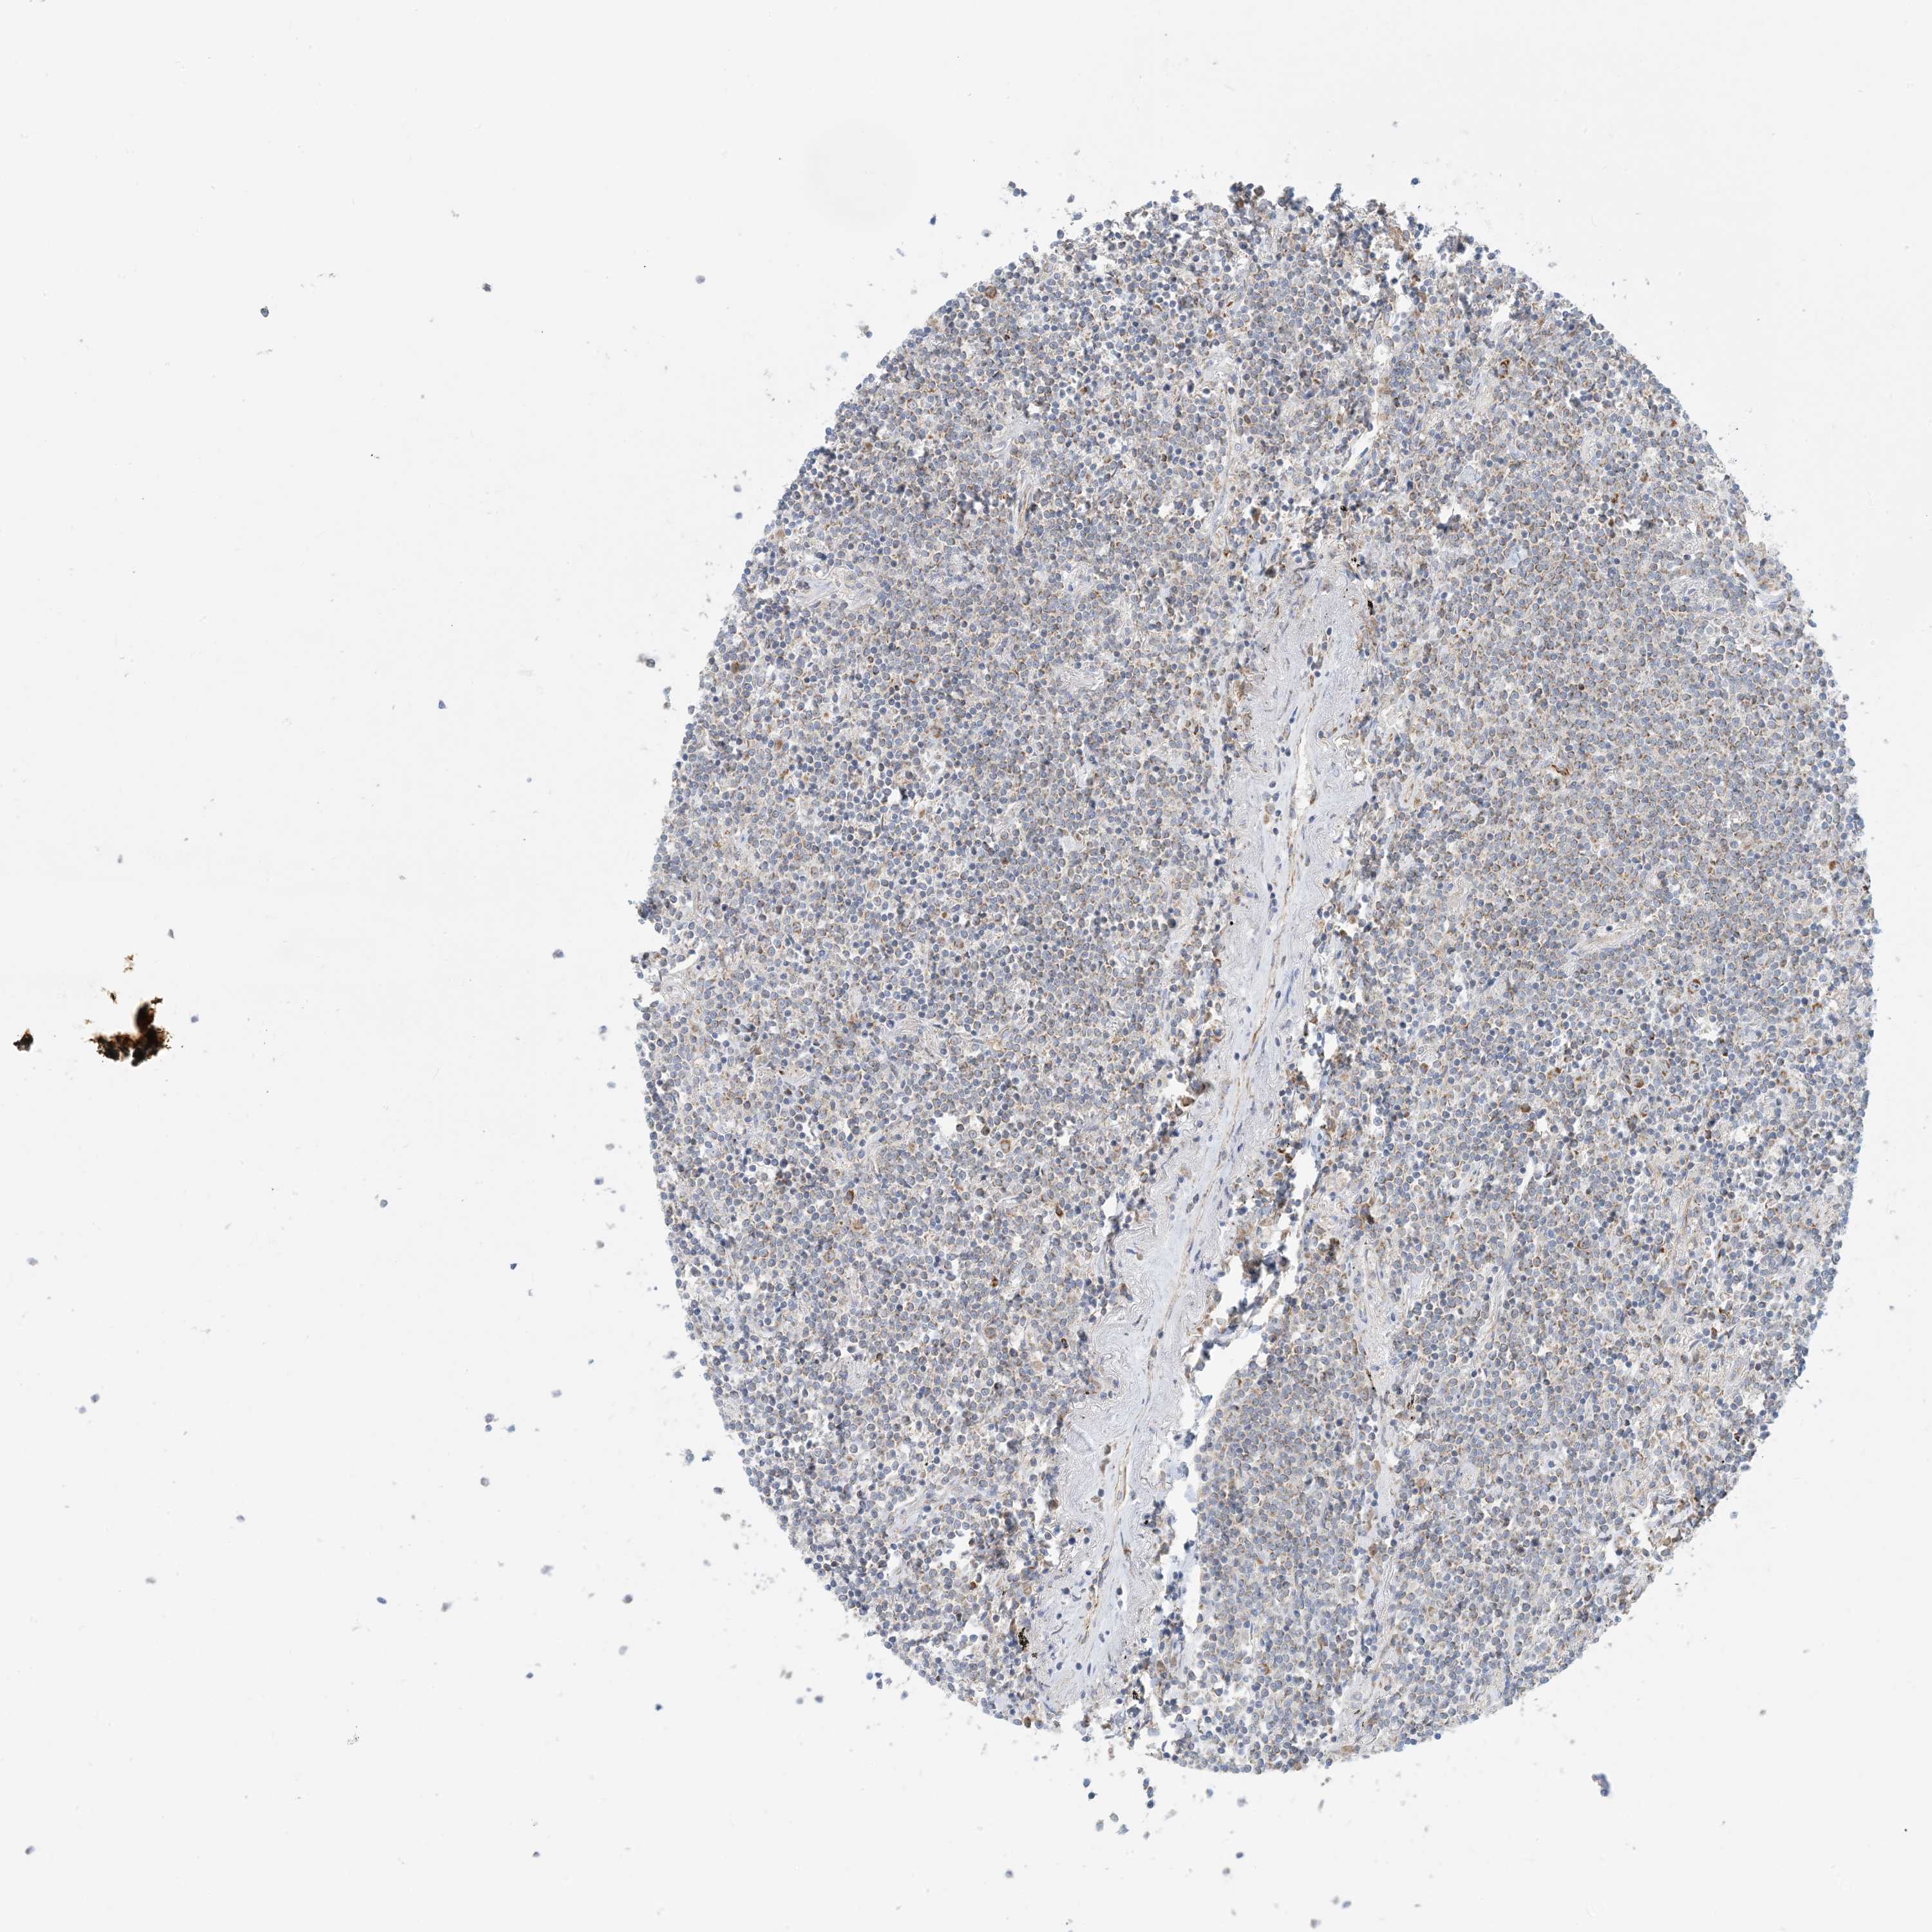

LYMPHOMA - Protein expressioni

A mouse-over function shows sample information and annotation data. Click on an image to view it in a full screen mode. Samples can be filtered based on level of antibody staining by selecting one or several of the following categories: high, medium, low and not detected. The assay and annotation is described here.

Each image is clickable and will lead to virtual microscopy that enables deeper exploration of all samples and also displays staining intensity scores, fraction scores and subcellular localization as well as patient and tissue information for each sample.

Antibody HPA031966

Staining

Medium

Intensity

Weak

Quantity

<25%

Location

Cytoplasmic/membranous

Hodgkin's disease, NOS

Malignant lymphoma, non-Hodgkin's type, High grade

Malignant lymphoma, non-Hodgkin's type, Low grade